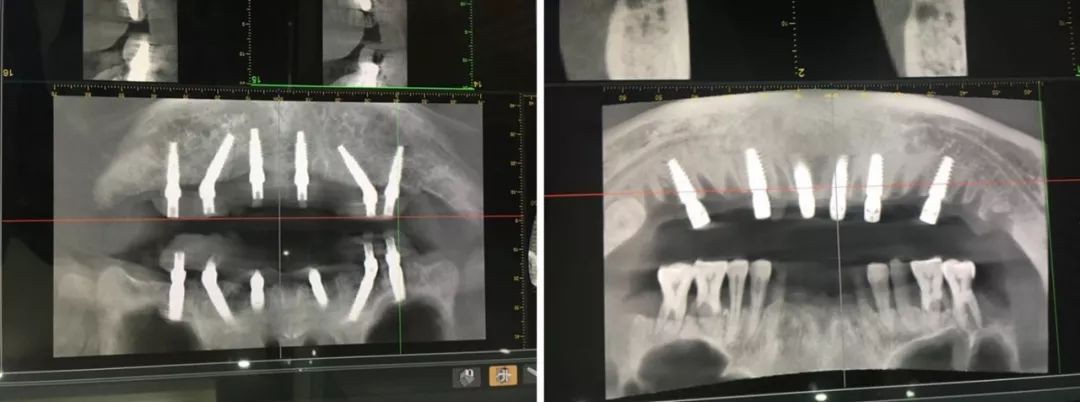

种植牙就是在我们缺失牙齿的区域,将种植体(人工牙根)植入骨头内,几个月后,种植体与牙槽骨完成紧密骨结合,能在骨头内能够稳固生存,再在种植体的上面接上烤瓷牙恢复牙齿的形态和功能。所以,种植牙就是用种植体代替天然牙根、烤瓷牙恢复牙冠的一种牙齿缺失的修复方法,可以获得与天然牙功能、结构以及美观效果。

医院开展CAD/CAM数字化种植导板技术,通过整合数字化影像、cbct 数据以及数字化加工技术的新型种植导板,充分考虑到了颌骨条件、口腔解剖结构以及修复效果的结合,用以提高手术精度,降低手术风险,减轻患者痛苦。